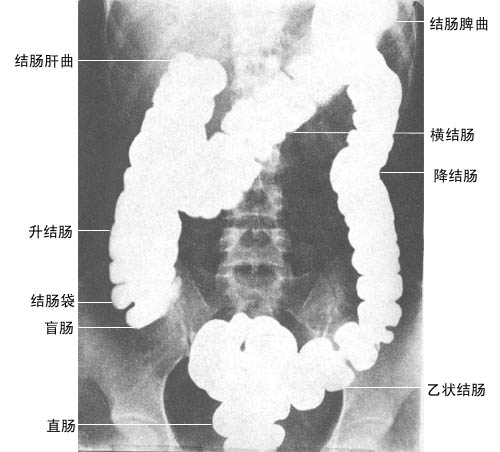

钡灌肠

大肠分为:盲肠(包括阑尾),升结肠,结肠右曲,横结肠,结肠左曲,降结肠